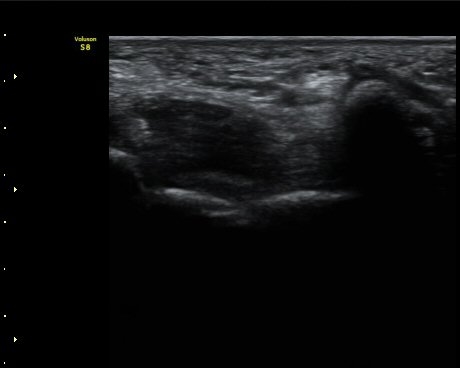

ŽÃËÀÚ¸¦ Á¶±Ý ´õ ¸»´ÜÀ¸·Î À̵¿ÇÏ´Ï Ã´°ñ½Å°æ ½ÉºÎ¿îµ¿°¡ÁöÀÇ ºÎÁ¾ÀÌ °üÂûµÇ°í ½Å°æ ¿äÃøÀ¸·Î Àú¿¡ÄÚ

¿øÇüÀÇ Á¾±«°¡ °üÂûµÈ´Ù(»çÁø 4, 5).